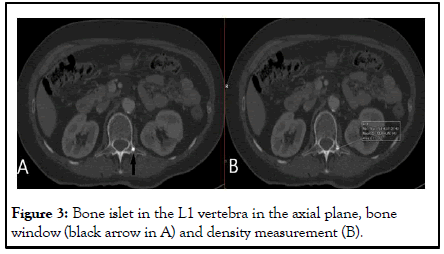

A 70-year-old female patient was diagnosed with left breast cancer in 2011 and no significant pathology was detected in the PET CT report taken after left mastectomy at that time. The patient was admitted to us with a new diagnosis of ovarian Ca. Thoracic CT scans performed for staging revealed sclerotic lytic bone lesions in the left 2nd, 3rd and 4th costae, which were not present before. Considering the absence of involvement in Pet CT in a patient with a history of RT and subcutaneous sequelae changes in the same region, sclerotic lesions in the costae were evaluated in favor of osteoradionecrosis and sclerotic bone metastasis was considered in the differential diagnosis with a lower probability (Figures 1 and 2). At the same time, there was a hyperdense, smoothly circumscribed, bone lesion in the left transverse process of the L1 vertebra (Figure 3). The lesion in the L1 vertebra was measured with a mean density of 1009 HU and was evaluated in favor of enostosis due to its characterization [5].

Figure 2: Sclerotic lesions in the left 2nd and 3rd costae in the thorax CT coronal plane (white arrow head, white arrow).

Figure 3: Bone islet in the L1 vertebra in the axial plane, bone window (black arrow in A) and density measurement (B).

The thoracic CT images demonstrated well-defined mixed lytic and sclerotic lesions with periosteal irregularity and cortical disruption confined to the previously irradiated ribs. The changes were associated with adjacent soft-tissue atrophy and skin thickening findings consistent with post-radiation sequelae. Importantly, a concurrent PET-CT revealed no increased metabolic activity in these rib areas, making metastatic involvement less likely. The absence of Fluorodeoxyglucose (FDG) uptake strongly favored a non-metastatic etiology [6].

Considering the clinical history of prior RT, absence of metabolic activity and the confined distribution of the lesions within the irradiated field, the diagnosis of osteoradionecrosis of the chest wall was made. Sclerotic bone metastases were still considered a differential option but deemed less probable.